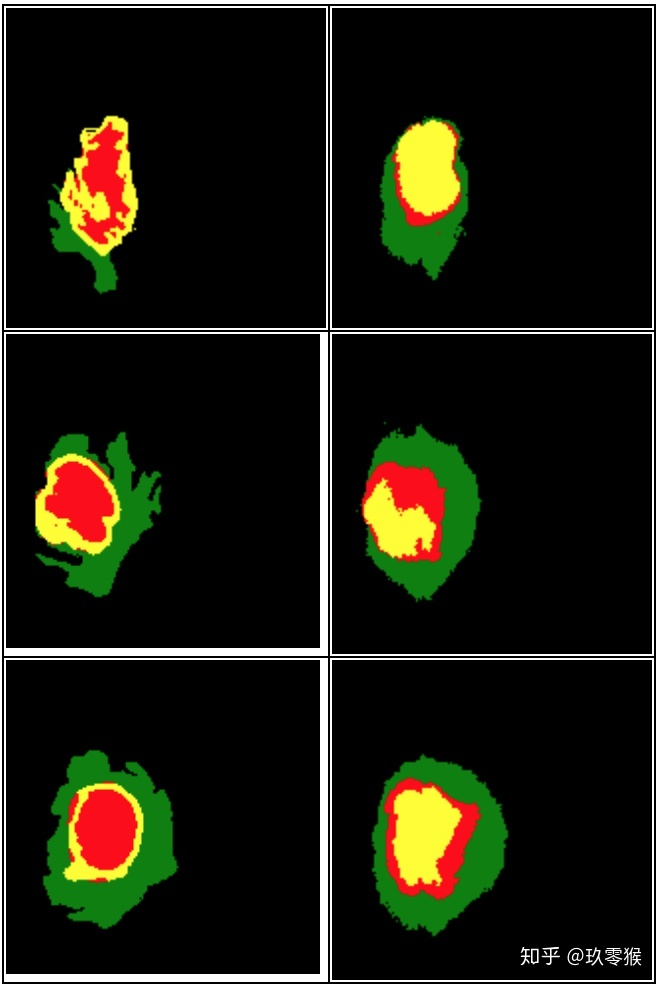

python .\test.py --name="Jiu0Monkey_FCN8s_woDS" --mode="GetPicture"

运行下面指令评价测试结果以及GT文件的指标,想了解更多指标的信息包括Dice、Hausdorff、IOU、PPV等,可以参考我这一篇(分割常用评价指标)

运行的结果: